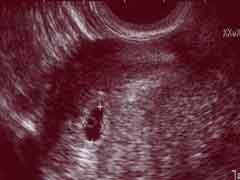

妊娠初期

妊娠初期(妊娠0ヶ月,妊娠1ヶ月,妊娠2ヶ月,妊娠3ヶ月)の兆候は?妊娠初期症状は?妊娠初期,妊娠中期,妊娠後期の紹介。